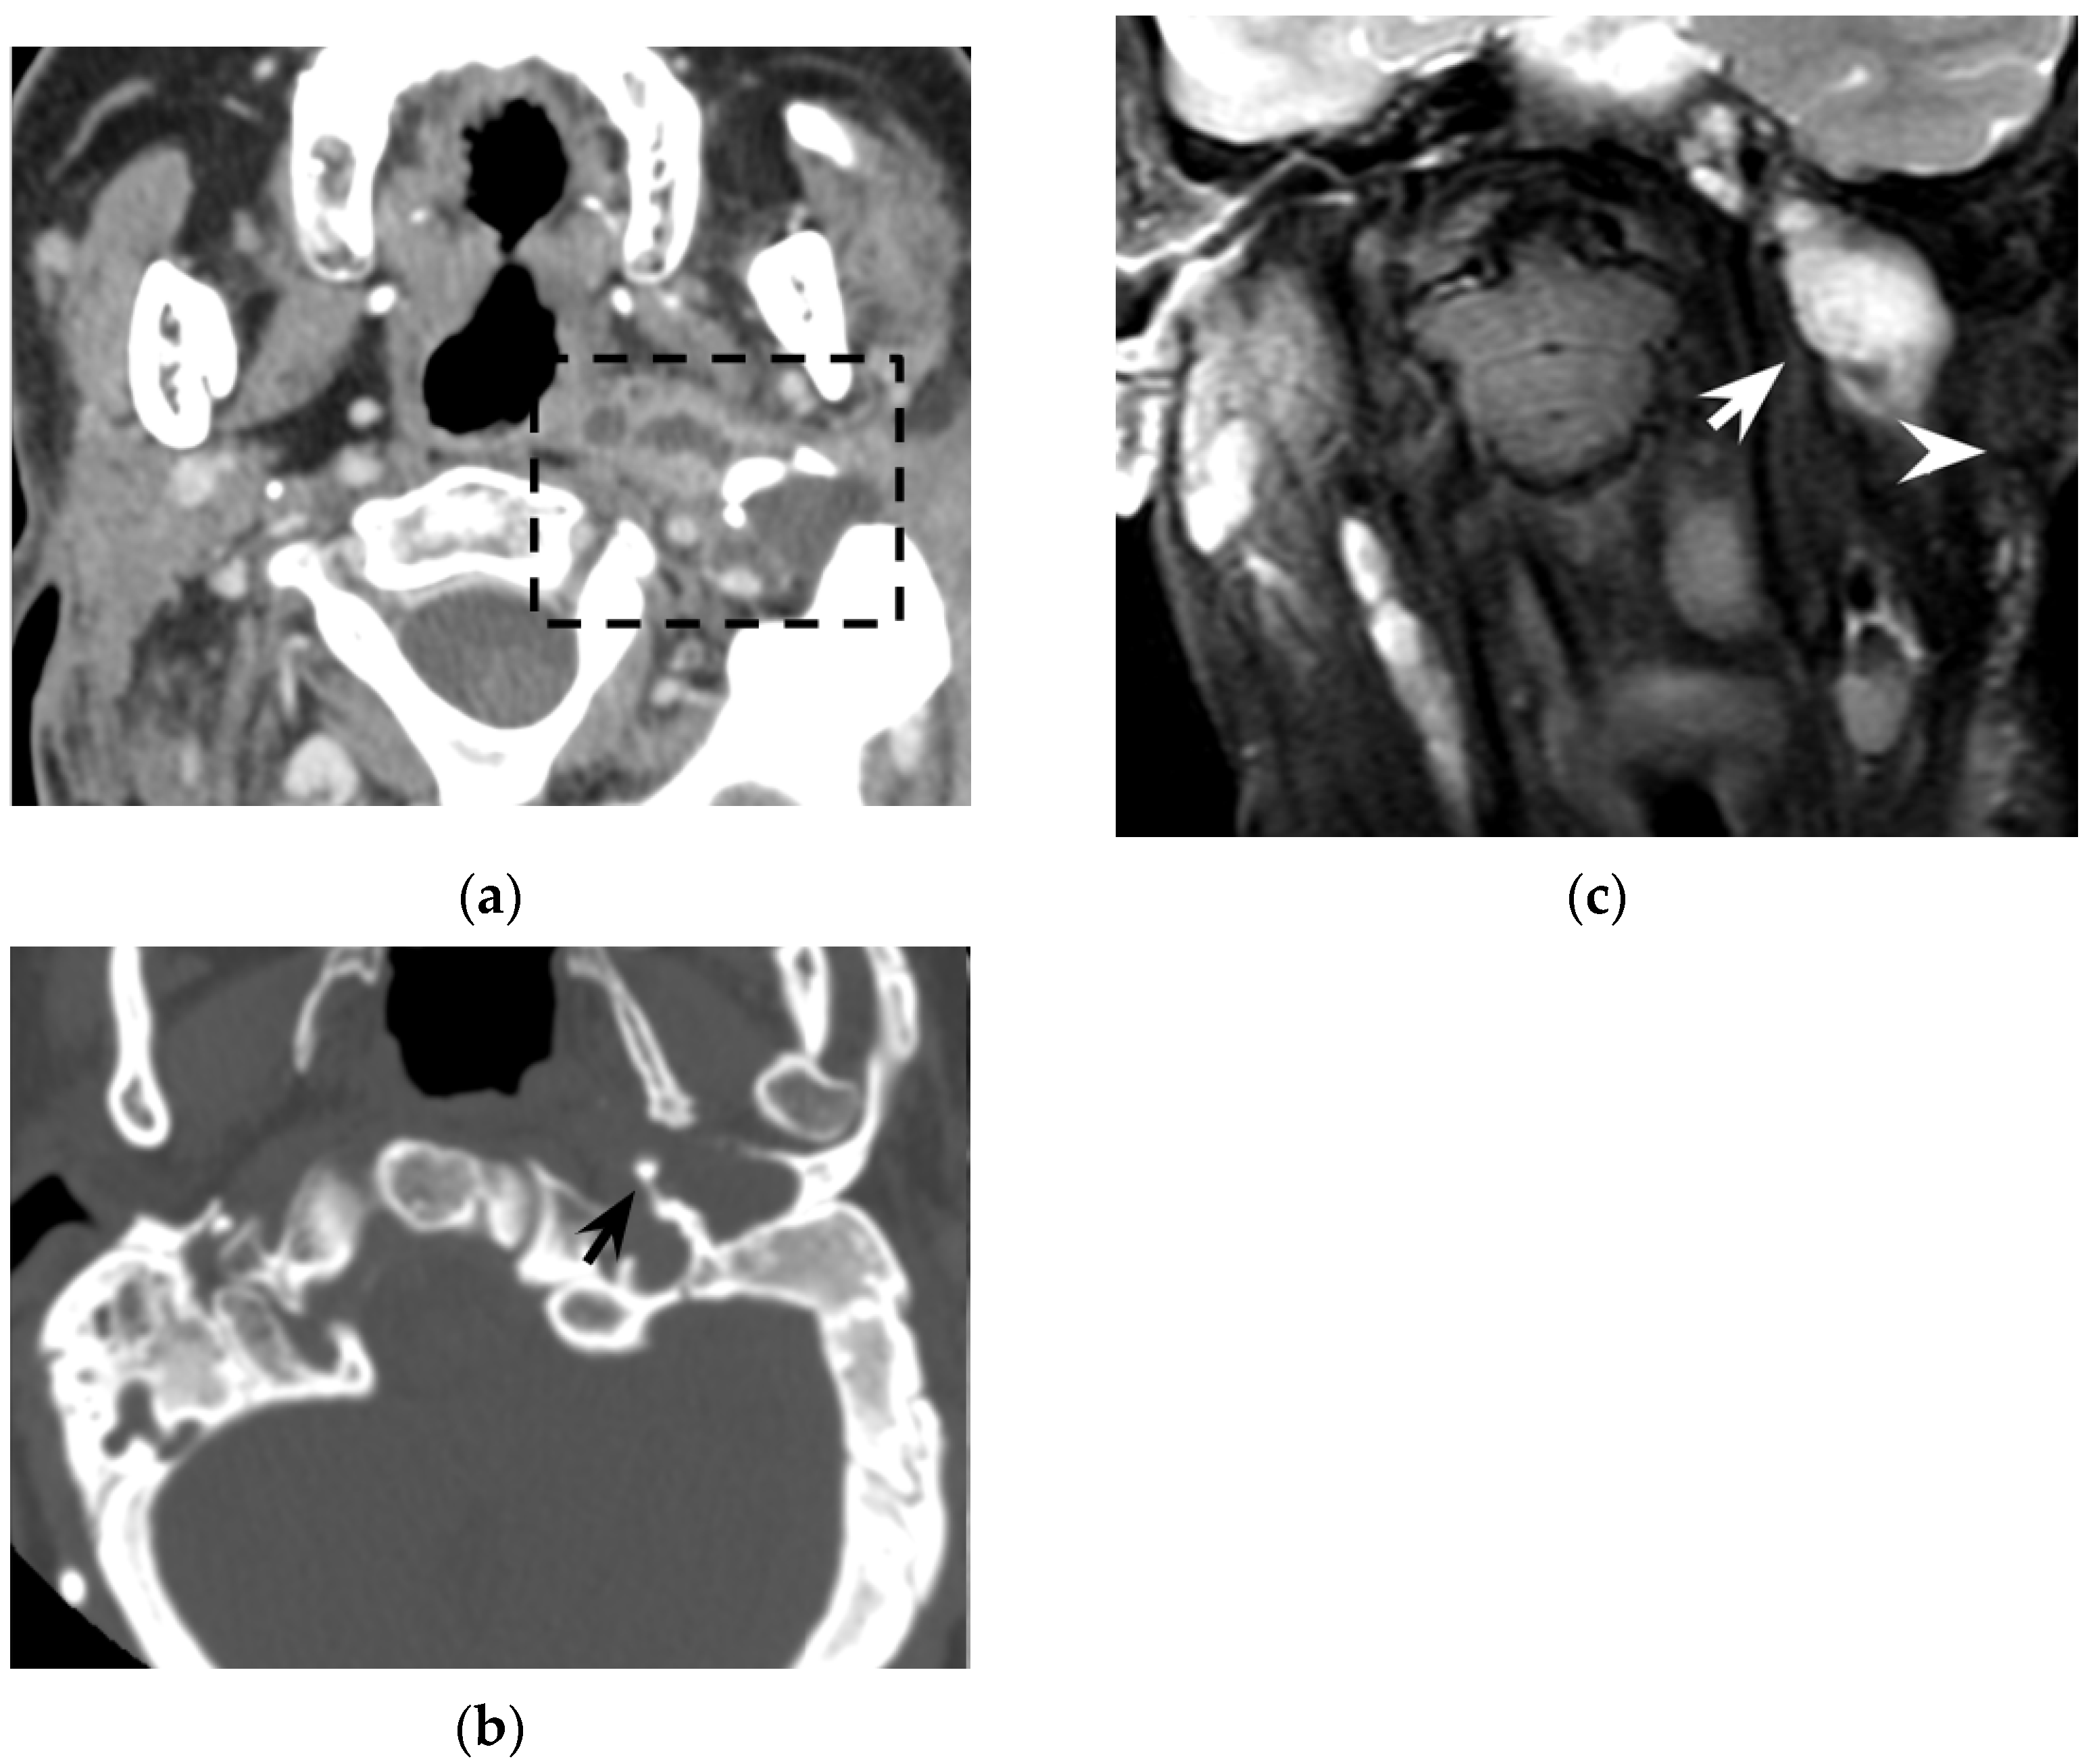

Figure 5. Thirty-year-old woman with oculo-auricular-vertebral spectrum. Contrast-enhanced axial CT (a) shows hypodense left neck abscess in the parapharyngeal and pharyngeal mucosal spaces, with minor involvement of the visceral and posterior cervical space (dotted rectangle). Note the peripheral enhancement and the soft tissue oedema. Axial CT with bone kernel (b) shows hypodense cholesteatoma eroding the os tympanicum (black arrow) as the origin of the neck abscess. Coronal T2w MRI (c) shows an hyperintense neck collection (white arrow) medial to the sternocleidomastoid muscle (white arrowhead). The patient proved to have a Bezold’s abscess associated with an os tympanicum cholesteatoma.